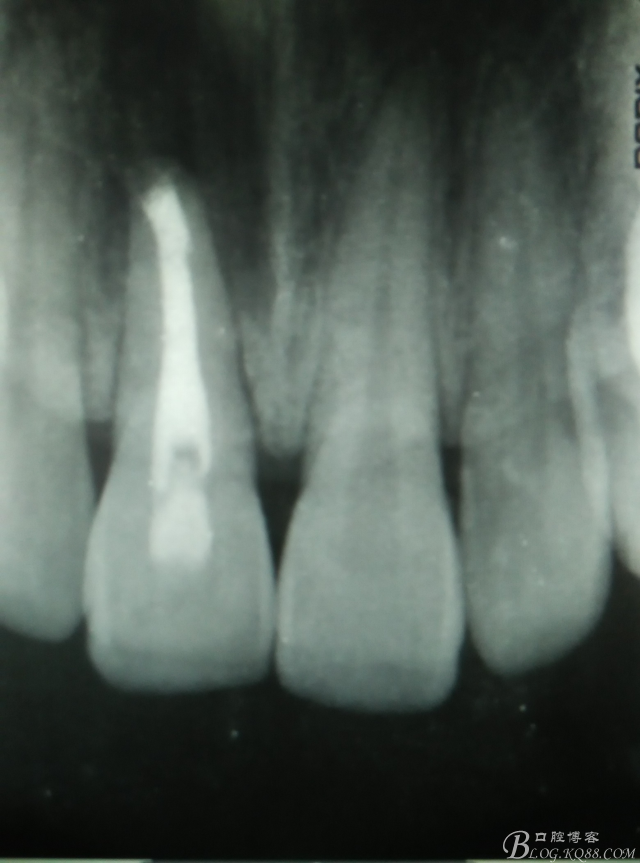

圖3.術(shù)前的11根尖片影像檢查:根充有點超填,根尖陰影明顯。范圍看著不大。